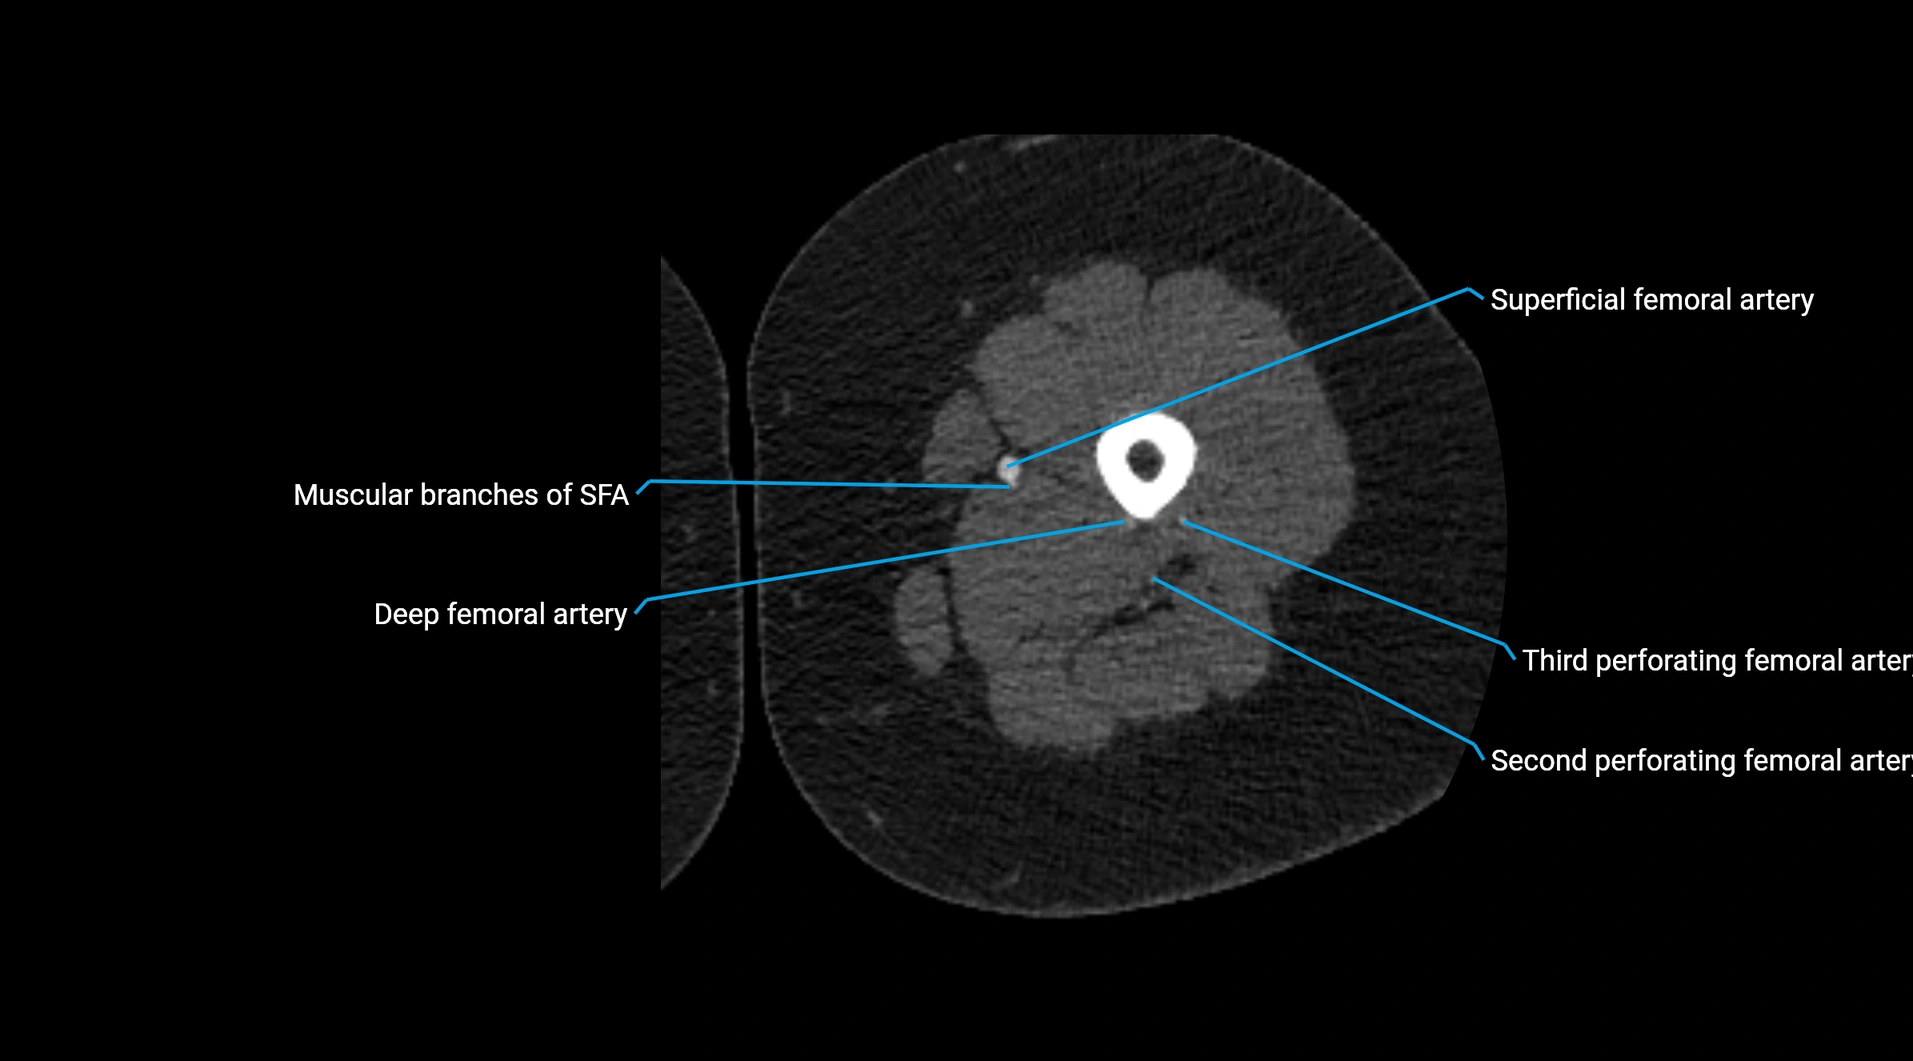

CT images

image